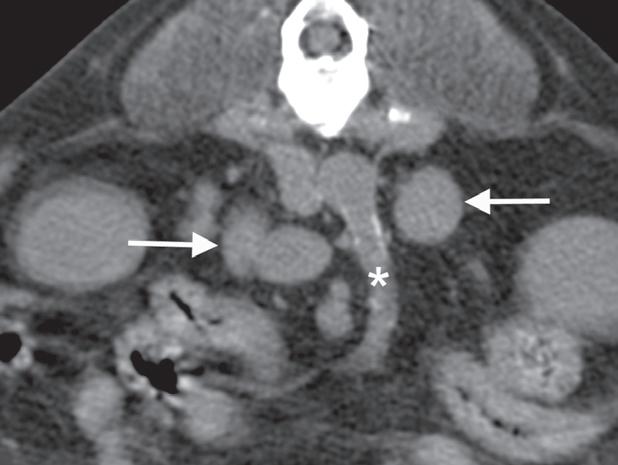

Badanie wykonano u 7-letniego rottweilera z rozpoznanym guzem nadnercza oraz nagłymi objawami dyskomfortu jamy brzusznej. Obrazy na ryc. a–c uporządkowano od strony doczaszkowej do doogonowej. Nadnercze prawe jest powiększone (a, d – otwarty grot strzałki) i ma widoczną ekscentryczną komponentę torbielowatą o densyjności płynu, która rozchodzi się doogonowo (a, b – strzałki). Tkanka miękka rozrostu oraz torebka nadnercza wykazują obwodowe wzmocnienie pokontrastowe. Torbielowata komponenta zmiany rozrostowej widoczna na obrazie odpowiada krwotokowi, który rozciąga się doogonowo w przestrzeni zaotrzewnowej (d). Dobrzusznie od zmiany widoczny jest moczowód (b – grot strzałki). Diagnoza makroskopowa i histologiczna została potwierdzona po chirurgicznym usunięciu zmiany (e – strzałka). Proszę zwrócić uwagę na porównanie obrazu TK zmiany (d) z wyciętym preparatem makroskopowym (f)

Rycina 5.6.6. Przysadkowozależna nadczynność kory nadnerczy (pies) TK